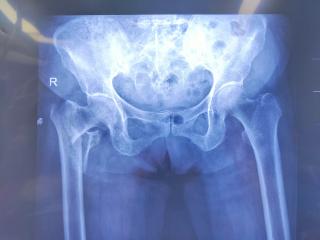

曹县中医医院:实施PFBN新技术 助八旬老人重获行走希望